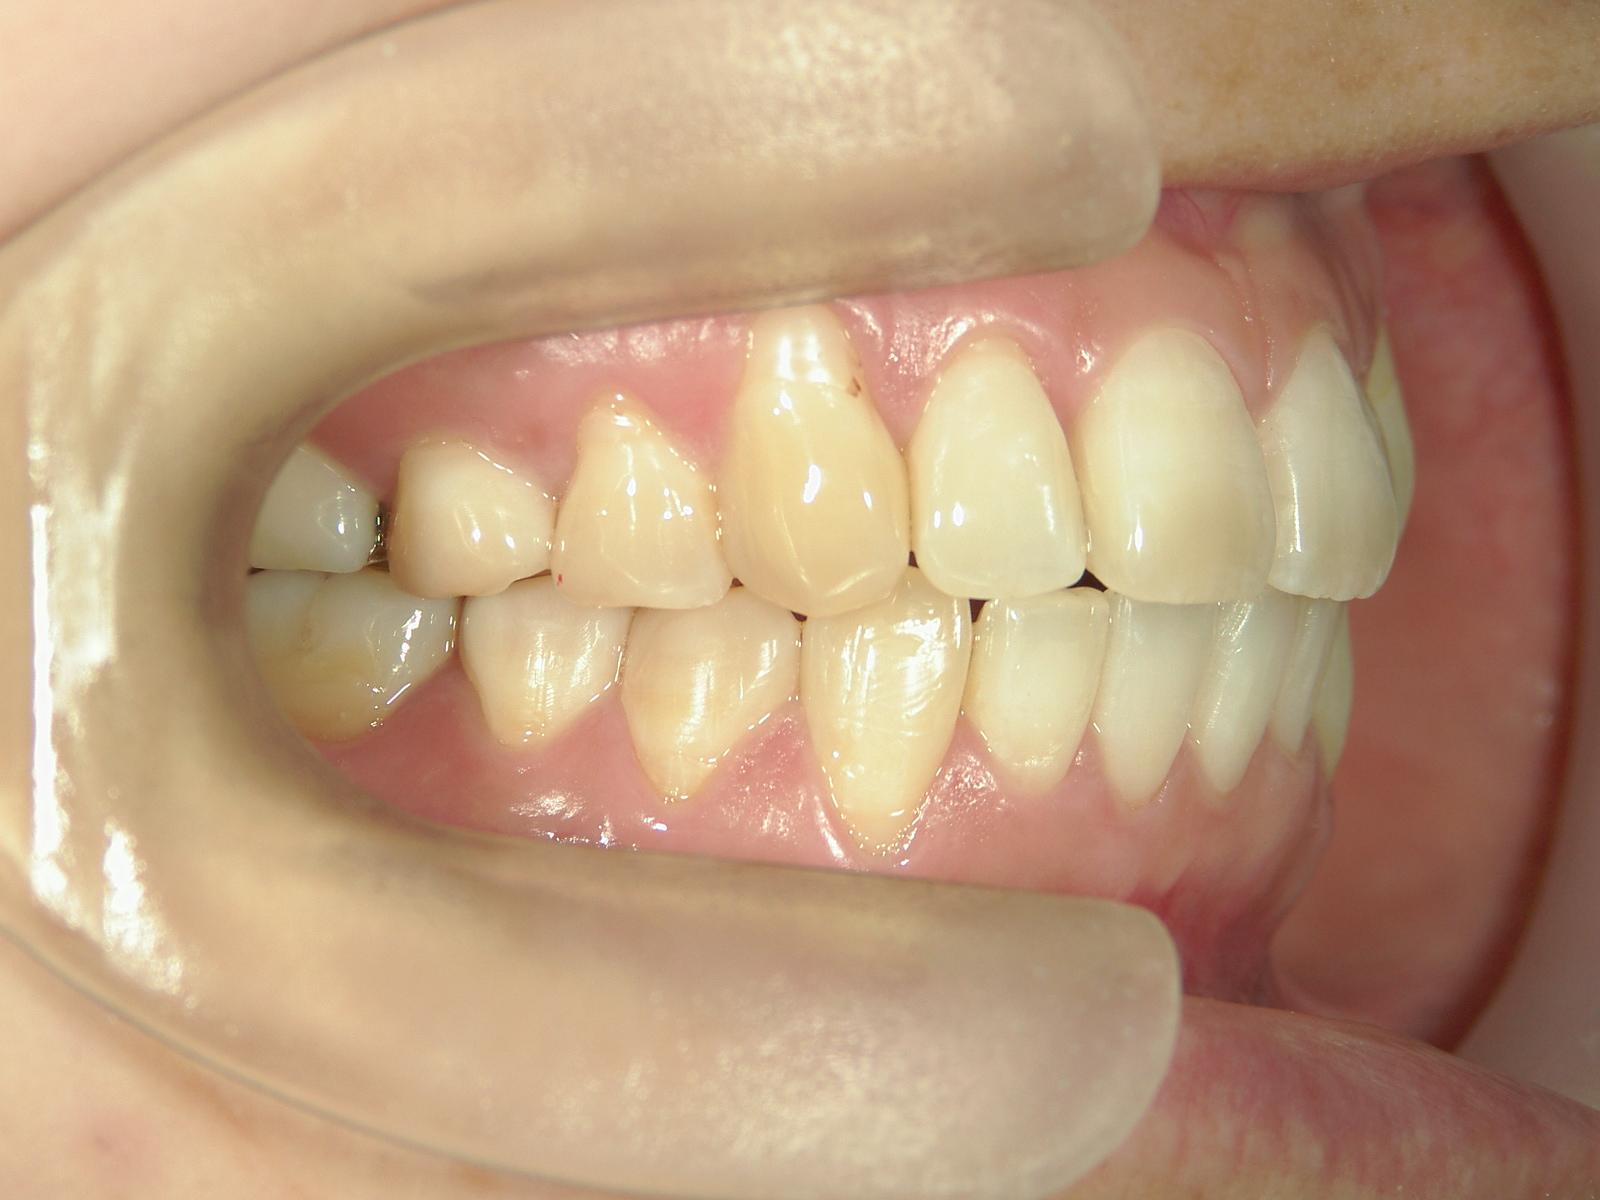

プチワイヤー矯正 症例(53)

主訴: 前歯の歯並びが気になる。

カテゴリー : ガタガタ(叢生)